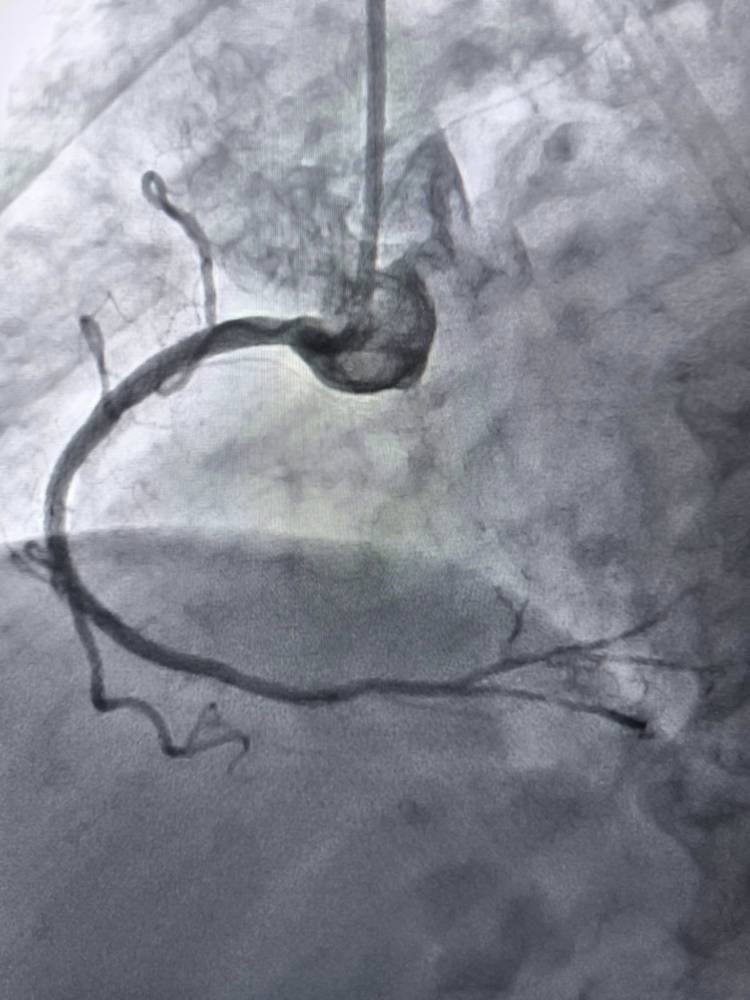

Головною проблемою для пацієнта була критична ішемія, коли кров просто перестає доходити до кінцівки через закам’янілі бляшки в артеріях. У таких випадках фінал зазвичай один — ампутація. Проте медики використали метод ротаційної атеректомії, що фактично означає делікатне висвердлювання проходу всередині судини спеціальним високотехнологічним обладнанням.

Операція потребує ювелірної точності, адже працювати доводиться з крихкими стінками артерій під постійним рентген-контролем. Хірурги успішно відновили кровотік, що дозволило пацієнту не лише зберегти ногу, а й значно покращити якість життя. Це перше втручання такого рівня складності в нашому регіоні, яке відкриває двері для багатьох хворих зі складними патологіями.